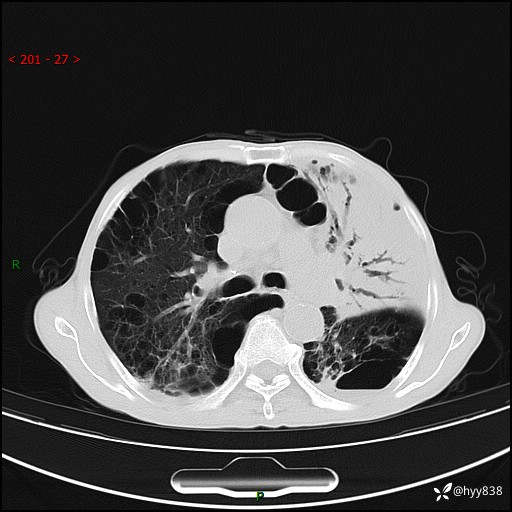

老年男性,反复咳嗽、咳痰、气喘10余年,再发3天。大叶性实变+胸膜病变-结果公布

主诉:反复咳嗽、咳痰、气喘10余年,再发3天

现病史:患者于10余年前开始出现反复咳嗽,咳痰,偶有少许黄色粘痰,伴活动后气喘,多于受凉及天气变化时发作,无胸痛、心悸、咯血等症状,休息后可自行缓解,起初因症状轻微可耐受,未到医院诊治,后症状逐渐加重,频发活动后气喘,活动耐力逐渐下降,未予药物治疗。3天前患者腹泻后出现气喘加重,伴咳嗽,咳黄色粘痰,痰较多,不易咳出,食欲差,无发热,无头昏、乏力、心慌,无头痛、晕厥,无端坐呼吸,无咯血,无胸痛、腹痛,无下肢水肿等,为求进一步诊治,来我院,急诊以“慢性阻塞性肺疾病伴急性下呼吸道感染”收入我科。 本次急性发作以来,患者精神、食欲差,大小便如常,体力下降。体重无明显变化。

胸部CT平扫+增强